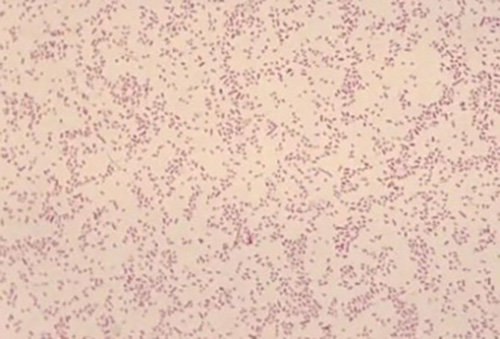

Fig. 1: Gram stain showing the faintly staining gram-negative coccobacilli Brucella melitensis.

The aerobic bottle from both blood cultures grew a gram-negative coccobacillus after 2 days of incubation (fig. 1). The organism was catalase positive and oxidase positive and grew best on 5% sheep's blood agar at 35*C in a CO2 enriched environment (fig. 2). It was identified by MALDI-TOF as Brucella melitensis. The sample was submitted to Los Angeles Public Health Department for confirmatory testing.

Brucellae are small gram-negative nonmotile coccobacilli which can be isolated as part of the normal flora of the genitourinary tract of a variety of wild and domestic animals including cows, goats, sheep, pigs, and dogs. The organism is strictly aerobic, nonencapsulated, and catalase and oxidase positive; it does not ferment carbohydrates and has variable urease activity. Based on DNA homology, it has been demonstrated that all six members of the genus are, in fact, serovars of a single species of which four, namely, Brucella abortus, B. suis, B. canis, and especially B. melitensis are able to cause human infections.